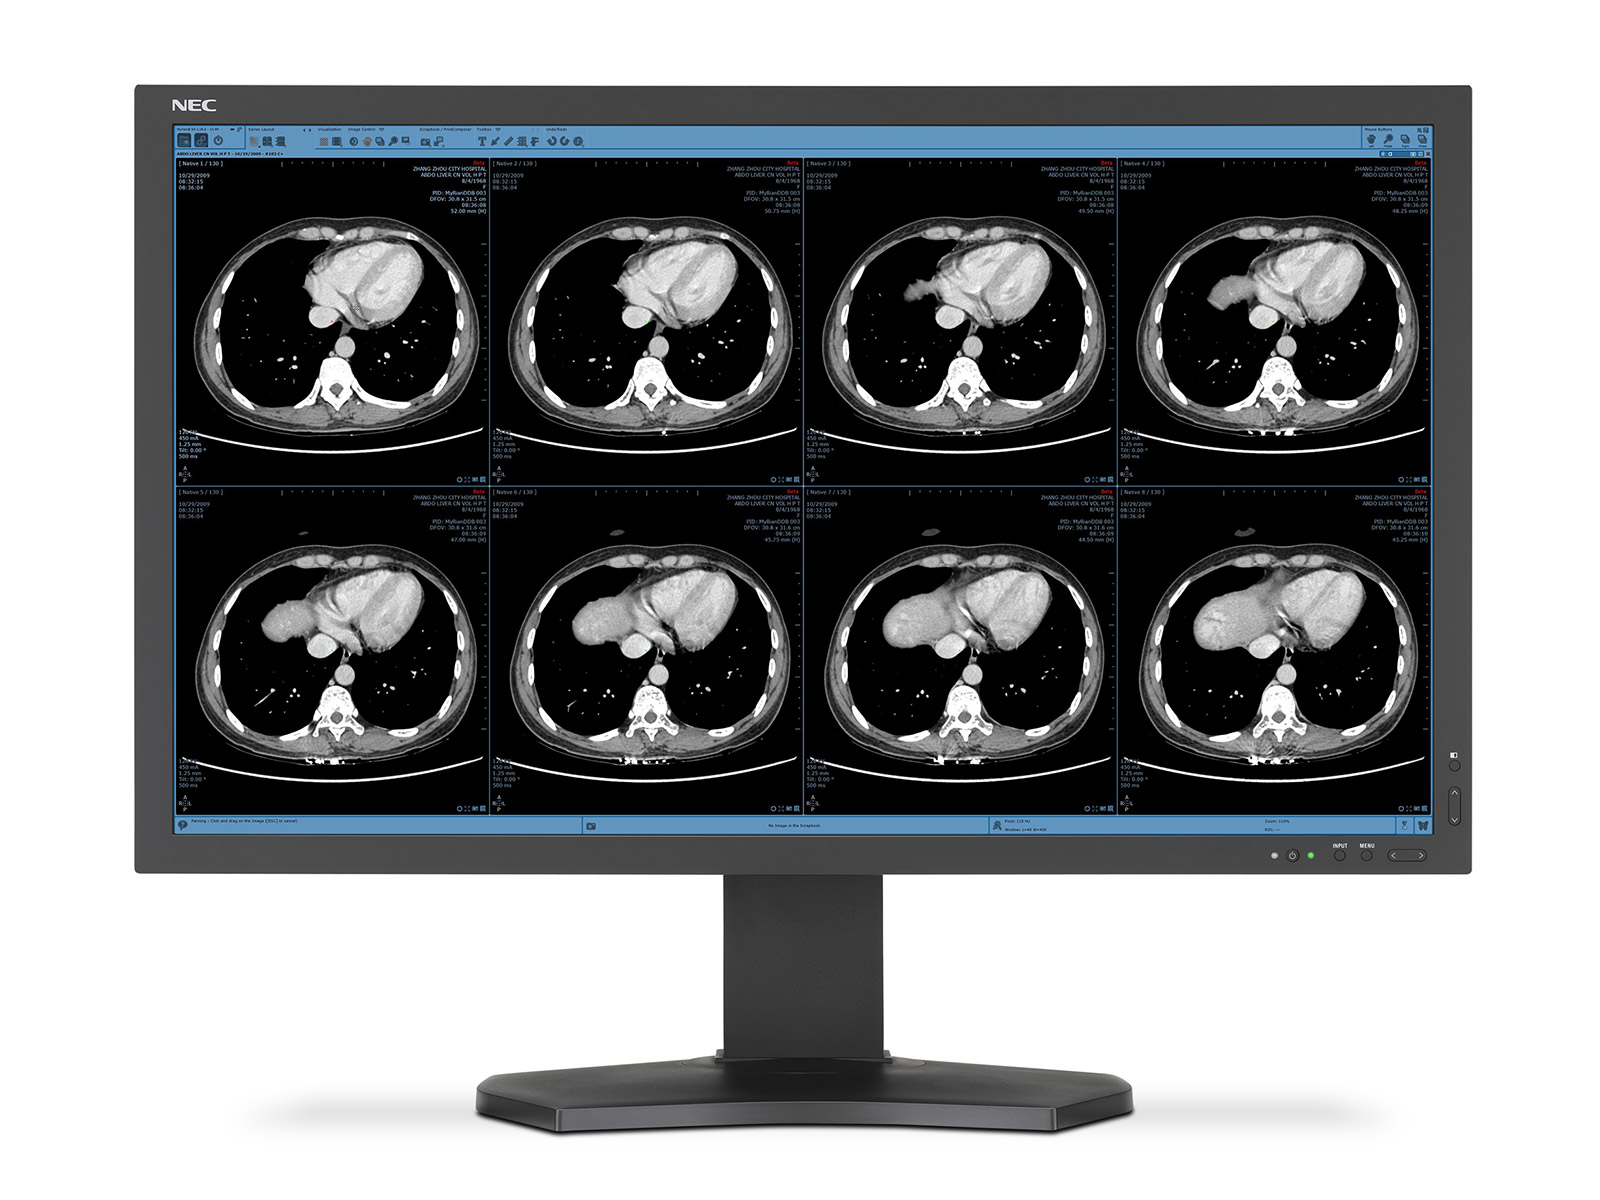

The Merian Iselin Hospital selected the NEC MultiSync® X841UHD 8MP monitor featuring a screen diagonal of more than two metres and DICOM mode for clinical review of x-ray images for use in the MDT room. An NEC MultiSync MD322C8, with the same resolution as the large-format display, is used as an input monitor for the radiologists.

MerianIselinHospitalDetail1

The extreme detail achieved with the UHD resolution display permits more precise diagnoses and allows extremely low viewing distances. Medical image data is reproduced correctly thanks to precise calibration and DICOM mode. “Black is really shown as black, just like white is really white on the screen”, says Dr. Egelhof with delight. A semi-matt surface restricts the effect of reflections on the screen.

The diagonal dimensions of more than two metres allow several images to be shown alongside each other for direct comparison. The sheer size permits groups of up to 10 people to gather in front of the screen with unrestricted views. Thanks to the high display brightness, images remain stable regardless of the ambient room lighting. Whilst in operation, the monitor does not emit any audible sound, therefore concentration is not impaired, even in larger groups or sensitive meeting situations.

Thanks to the wide variety of connection options, several signal and cable types allow a flexible choice of playback sources. Picture Archiving and Communication System (PACS) software permits the communication of findings and distributes image data to the connected peripheral devices. The monitor supports the Visus viewer used and can thus be integrated in the solution without any problems. The Radiology Information System (RIS) from medavis is used for the workflow management.